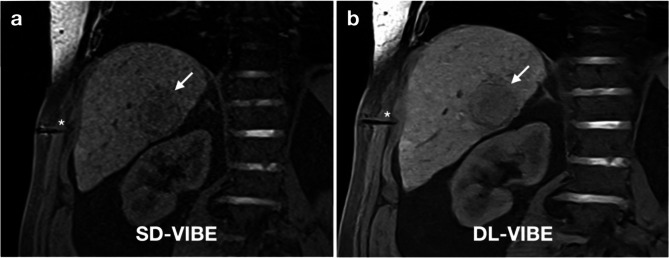

Objective: This study evaluates the impact of deep learning-enhanced T1-weighted VIBE sequences (DL-VIBE) on image quality and procedural parameters during MR-guided thermoablation of liver malignancies, compared to standard VIBE (SD-VIBE).

Methods: Between September 2021 and February 2023, 34 patients (mean age: 65.4 years; 13 women) underwent MR-guided microwave ablation on a 1.5 T scanner. Intraprocedural SD-VIBE sequences were retrospectively processed with a deep learning algorithm (DL-VIBE) to reduce noise and enhance sharpness. Two interventional radiologists independently assessed image quality, noise, artifacts, sharpness, diagnostic confidence, and procedural parameters using a 5-point Likert scale. Interrater agreement was analyzed, and noise maps were created to assess signal-to-noise ratio improvements.

Results: DL-VIBE significantly improved image quality, reduced artifacts and noise, and enhanced sharpness of liver contours and portal vein branches compared to SD-VIBE (p < 0.01). Procedural metrics, including needle tip detectability, confidence in needle positioning, and ablation zone assessment, were significantly better with DL-VIBE (p < 0.01). Interrater agreement was high (Cohen κ = 0.86). Reconstruction times for DL-VIBE were 3 s for k-space reconstruction and 1 s for superresolution processing. Simulated acquisition modifications reduced breath-hold duration by approximately 2 s.

Conclusion: DL-VIBE enhances image quality during MR-guided thermal ablation while improving efficiency through reduced processing and acquisition times.